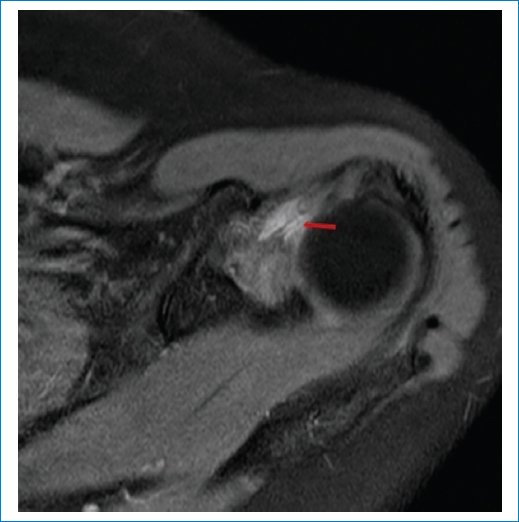

En nuestra serie aplicamos los criterios de Emig et al.11, que incluyen la hiperintensidad o el engrosamiento del ligamento glenohumeral inferior > 3 mm (Figs. 1 a 3), el engrosamiento capsular del receso axilar (con valores que varían según los estudios, pero descrito en general como > 7 mm) (Fig. 3), el engrosamiento del ligamento coracohumeral > 4 mm (Fig. 4), la infiltración grasa y la hiperintensidad del intervalo rotador (Figs. 5 a 7), y la obliteración de la grasa subcoracoidea (descrita como ausente, parcial o completa) (Fig. 8).

Figura 7. RM en secuencia DP-FS, corte axial. Se observa hiperintensidad leve en el intervalo rotador.